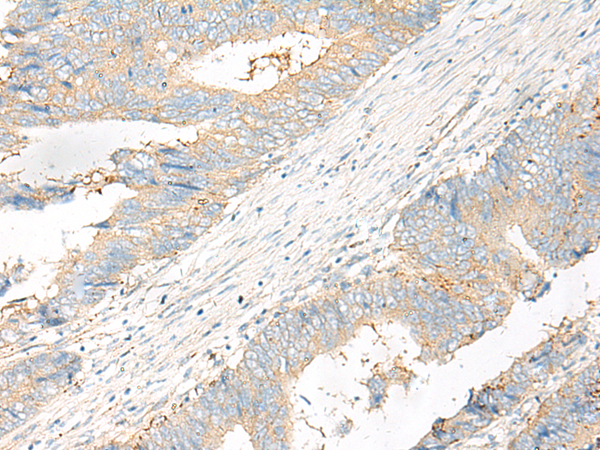

分类: 科研抗体货号: P06580别名: RFG5; GOLIM5; ret-II应用: WB,IHC反应种属: Human